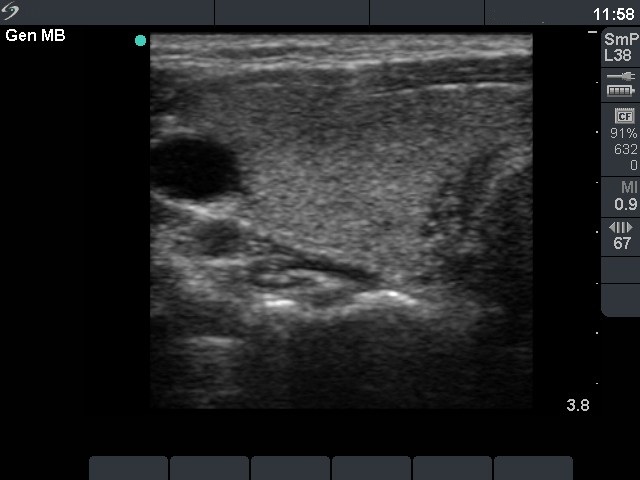

Graves' disease - Case 1049

Follow-up investigation 18 months after first visit (ultrasonographic picture 1)

Patient on daily 5 mg methimazole therapy in euthyroid state

Right lobe, transverse scan. The thyroid became echonormal, only the ventral part of the lobe is minimally hypoechogenic.